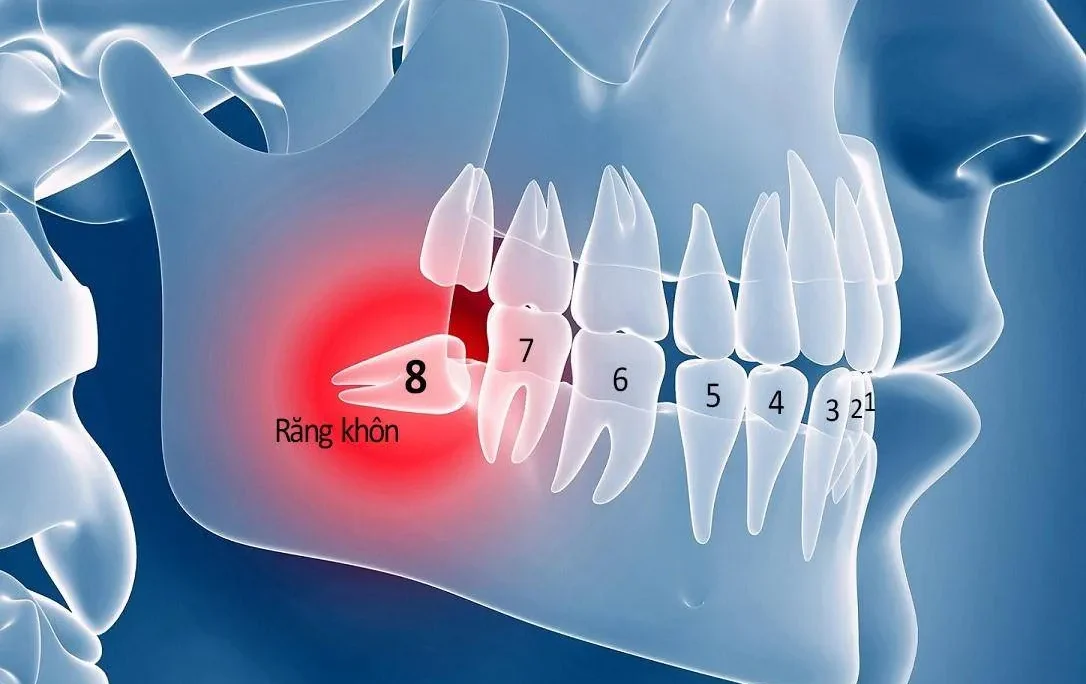

Khi không may bị mất răng, nhiều người thường lo lắng về những ảnh hưởng đến thẩm mỹ và chức năng ăn nhai. Tuy nhiên, với sự phát triển của y học nha khoa, có nhiều giải pháp hiệu quả để khắc phục tình trạng này. Trong số đó, cầu răng sứ là một trong những lựa chọn phổ biến, được đánh giá cao về độ bền, tính thẩm mỹ và khả năng phục hình chức năng ăn nhai gần như răng thật.

- Cầu răng trên implant: Đây là một kỹ thuật hiện đại hơn. Thay vì sử dụng răng thật làm trụ, chiếc cầu răng được nâng đỡ bởi các trụ implant đã được cấy ghép vào xương hàm. Phương pháp này đặc biệt hữu ích khi bệnh nhân bị mất nhiều răng liên tiếp hoặc không có răng thật khỏe mạnh để làm trụ.